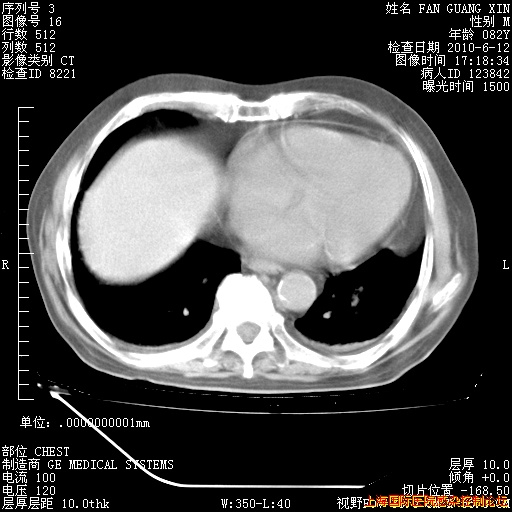

今天复查CT

今天CT

整整相隔30天的肺部CT好像有所好转啊。甲强龙减量第3天,需要观察体温。

海管,自昨日你和我通完话后,不知您岳父消化道症状有无缓解?体温怎样?阅读7.12日胸部ct,个人认为目前激素治疗是有效的,甲强龙减量是适宜的。因在抗痨治疗,需密切观察肝功、肾功能和血常规。不过,老年、长期住院和大量使用激素,很担心菌群失调发生